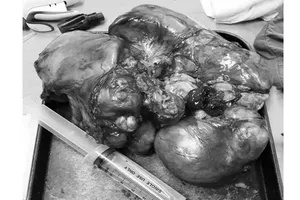

Phẫu thuật thành công khối u kích thước bằng quả cam trong lồng ngực Y tế - Sức khỏe 17/06/2017 19:02